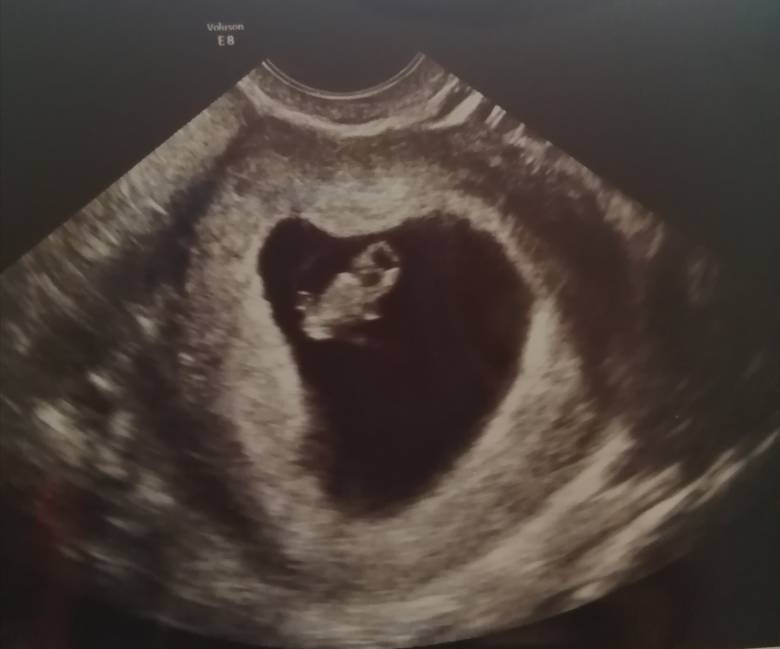

Mam 37 lat i to moja 3 ciążą (2 niestety zakończyła się poronieniem samoistnym). Według badania 30.03.20 termin mam na 14.11.2020

Serduszko biło i kruszynka się pojawiła w 7 tyg i 1 dz. Mimo wszystko bardzo się boję, gdyż mam dość silne bóle brzucha, czasami napinanie oraz bóle pleców. Kłócia i ciągnięcia też są częste... Dostałam Luteine dowcipną i ostatnio upławy są masakryczne (zółte)... Biegam do lazienki by sprawdzić czy to przypadkiem nie @... Okropnie się boję ehhhh